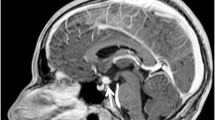

A bone scintigraphy with technetium 99m-methyl diphosphonate (Tc-99m MDP) was performed to further investigate bone involvement. Increased bone conversion was seen in the same regions as those earlier identified. The lesions in the spine that were identified with whole-body MRI were not visible on scintigraphy. A brain MRI showed a normal adeno- and neurohypophysis. No other significant lesions were detected.